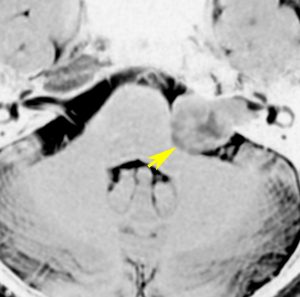

また,この患者さんは急に容態が悪くなって意識障害となりました。何故なら腫瘍の内部で出血したからです(黄色の矢印の部分)。第4脳室が詰まって閉塞性水頭症になって側脳室が拡大しています(右の画像)。